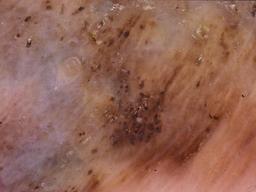

BRAAFF-Annotated Acral Lesions Dataset (BALD)

The BRAAFF-Annotated Acral Lesions Dataset (BALD): A curated set of dermatoscopic images of acral melanoma and nevi from various sources.

Müller C, Tschandl P, Rinner C, Kyrgidis A, Koga H, Moscarella E, Apalla Z, Di Stefani A, Kobayashi K, Lazaridou E, Longo C, Phan A, Saida T, Sotiriou E, Tanaka M, Thomas L, Zalaudek I, Argenziano G, Lallas A, Kittler H. The BRAAFF-Annotated Acral Lesions Dataset (BALD): A Curated Set of Dermatoscopic Images of Acral Melanoma and Nevi from Various Sources. J Invest Dermatol. 2025 Jan 17:S0022-202X(25)00021-1